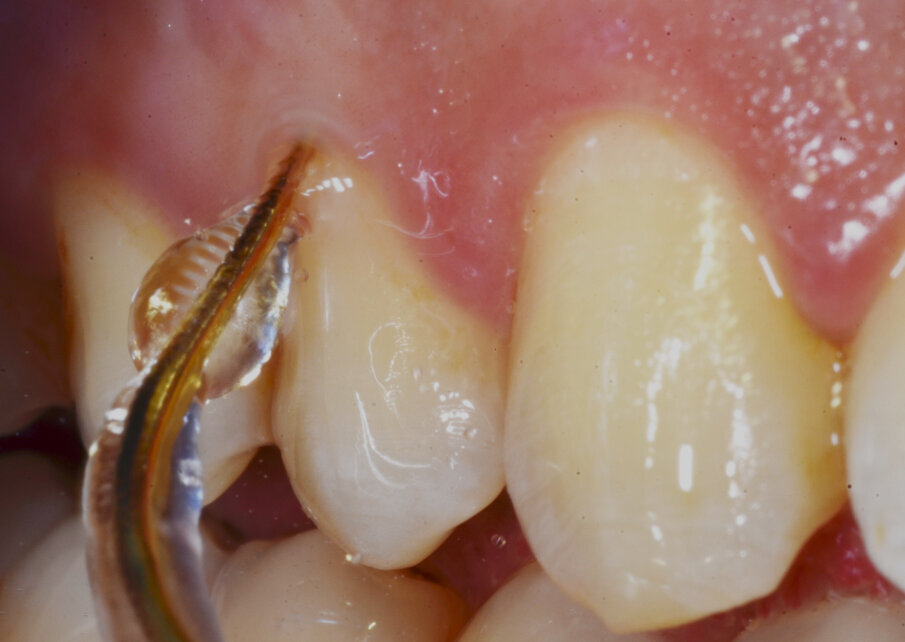

• Perio: utilizzare preferibilmente i Tips sottogengivali (Fig. 2), normalmente indicati in siti parodontali over 5, ma che ci permettono in questo momento di limitare eccessi del getto indirizzandolo interamente in tasca parodontale.